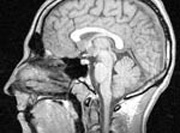

Американские ученые нашли новый подход к борьбе с наркотической зависимостью. В экспериментах на специально выведенных мышах они обнаружили, что блокирование особого рецептора в мозгу приводит к значительному снижению привыкания к наркотическим анальгетикам.

Уже было известно, что мускариновый рецептор к ацетилхолину типа M5 играет важную роль в формировании чувства удовольствия при введении морфина. Ученые предположили, что справиться с зависимостью можно путем инактивации этого рецептора. Они получили специальную генно-инженерную линию мышей, у которых не был активен ген, отвечающий за образование рецептора. Американские ученые нашли новый подход к борьбе с наркотической зависимостью. В экспериментах на специально выведенных мышах они обнаружили, что блокирование особого рецептора в мозгу приводит к значительному снижению привыкания к наркотическим анальгетикам.

Уже было известно, что мускариновый рецептор к ацетилхолину типа M5 играет важную роль в формировании чувства удовольствия при введении морфина. Ученые предположили, что справиться с зависимостью можно путем инактивации этого рецептора. Они получили специальную генно-инженерную линию мышей, у которых не был активен ген, отвечающий за образование рецептора.

Было установлено, что у таких мышей зависимость от наркотика проявлялась в меньшей степени. Если обычные мыши после получения дозы проводили все больше времени в той части клетки, где им вводился морфин, то в поведении генно-инженерных мышей таких элементов поведения не прослеживалось, если только они не получали очень высокую дозу наркотического препарата. Руководил этим исследованием Антони Базил (Anthony S. Basile), который сейчас работает на кембриджскую компанию Alkermes. Он убедился, что при заблокированных рецепторах не происходит уменьшение обезболивающего действия морфина. Кроме того, в эксперименте было отмечено, что у мышей из этой группы был менее выражен синдром отмены при прекращении введения морфина. Исследователи отметили, что никотин, алкоголь и кокаин воздействуют на мозг примерно по такому же принципу, поэтому блокирование мускаринового рецептора к ацетилхолину типа M5 может найти применение и для лечения вызванной этими веществами зависимости. Они объяснили также, что рецептор этот представлен в основном в мозгу, поэтому серьезных побочных эффектов со стороны других органов не будет. Результаты этого исследования, которое было частично профинансировано фармацевтическим гигантом Eli Lilly, появились в раннем издании Proceedings of the National Academy of Sciences. Mednovosti.ru По материалам Журнала Русской Америки